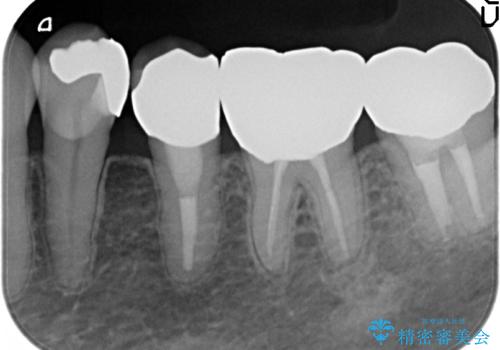

オールセラミッククラウン 再根管治療後の補綴

- 左下5番目の歯を根管治療からやり直したいといらっしゃった方の症例です。

再根管治療終了後、オールセラミッククラウンによる補綴を行いました。

今回用いたオールセラミッククラウンはジルコニアフレームという白い素材の上にセラミックを盛っているため、審美性が非常に高いのが特徴です。

また、ジルコニアは人工ダイヤモンドの材料にも使われているほど高い強度を持っており、そのためオールセラミッククラウンは審美性だけでなく、奥歯やブリッジの補綴も可能とするクラウンです。